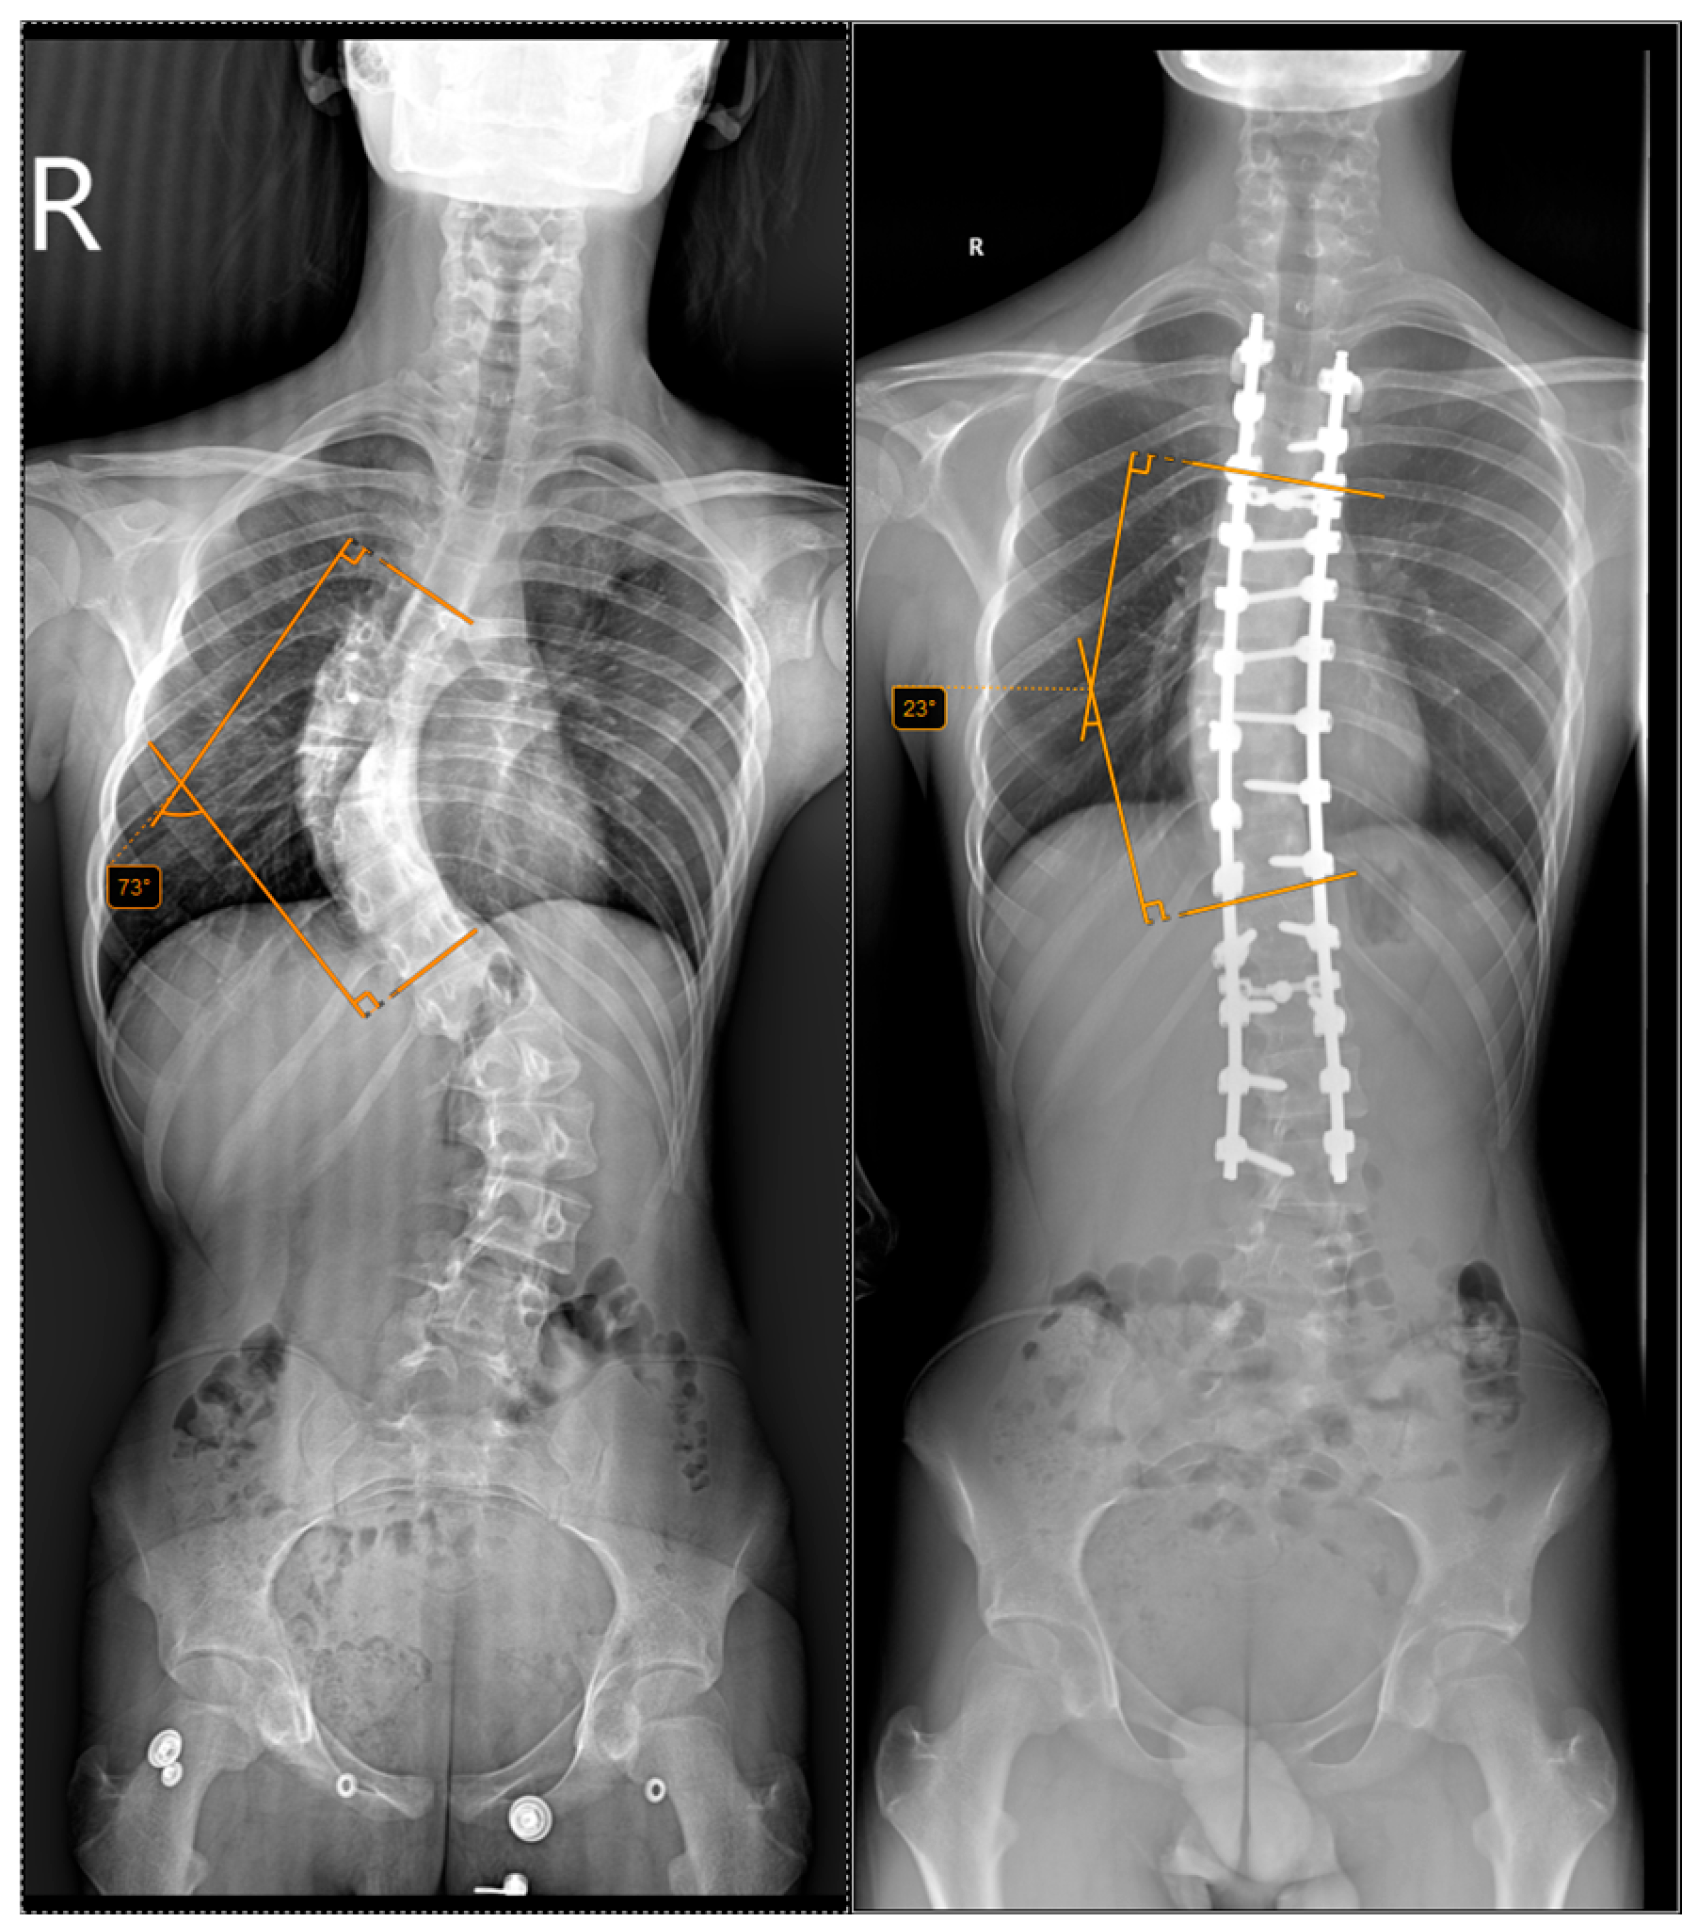

The inclusion criteria required a minimum follow-up of 12 months, complete clinical and radiological data, and informed consent to participate in the study. Standing anteroposterior and lateral full-spine radiographs were obtained preoperatively and postoperatively at 2 weeks, 1 month, 3 months, 6 months and annually thereafter. This is exemplified in Figure 2 and Figure 3.

Figure 3. Preoperative and postoperative radiographs of a 13-year-old patient who underwent halo-traction. The (left) image shows a preoperative Cobb angle of 73° for the main curve (T5–T11), while the (right) image shows the postoperative correction to 23°.